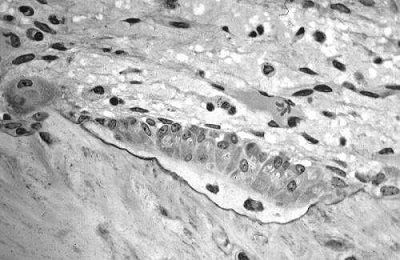

以“一串红”为研究对象,来自UBC的科学家们发现了一种特异性阻断Cathepsin K酶的方法。Cathepsin K是一种在破骨过程中负责降解胶原蛋白的酶类。相关结果发表在最近一期的《Journal of Bone and Mineral Research》杂志上。

研究者们分析了一种来自中草药“一串红”的化学成分对于破骨过程的影响。通过人以及小鼠的骨细胞培养以及小鼠模型试验,作者发现其能够有效阻断骨质的流失以及提高小鼠骨骼矿质元素密度35%。